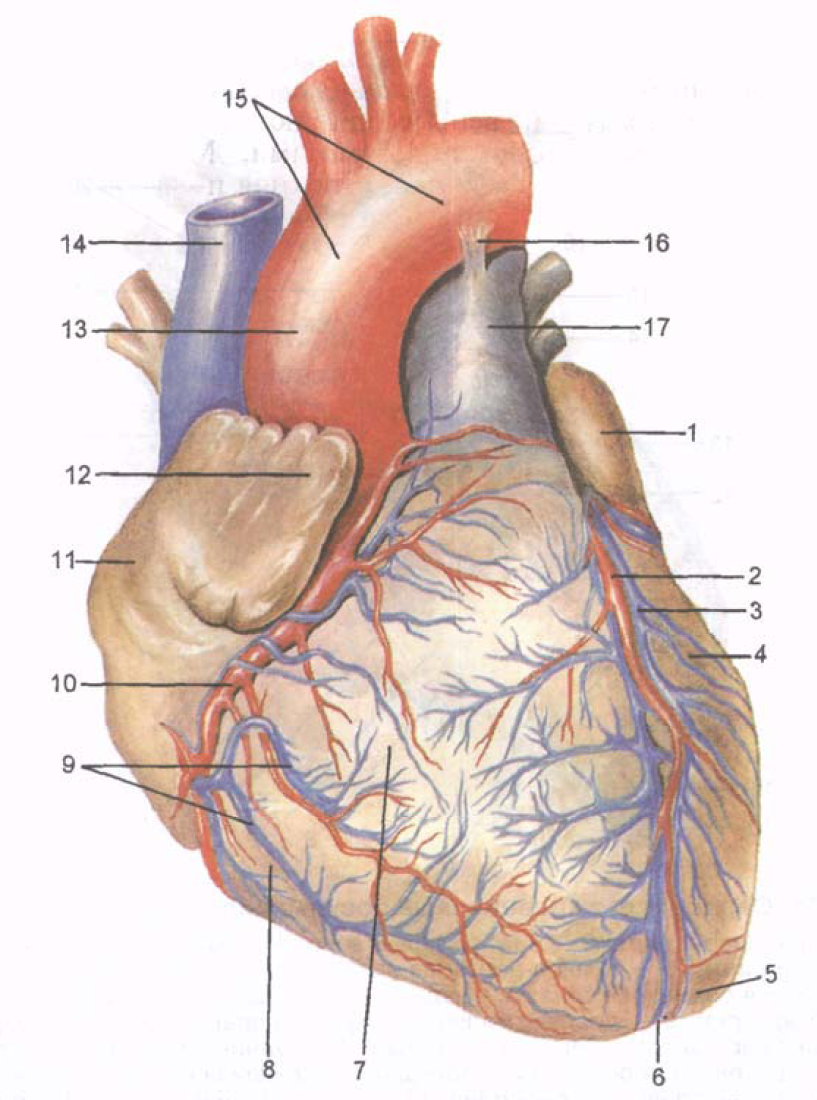

Анатомия коронарных артерий: КТ-изображения